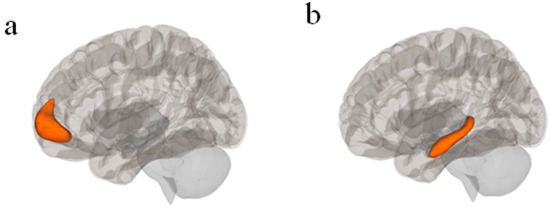

Functional and Structural Connectivity Correlates of Axial Symptom Outcomes After Pallidal Deep Brain Stimulation in Parkinson’s Disease

by Gilberto Perez Rodriguez Garcia, Erik Middlebrooks, Shanshan Mei, Takashi Tsuboi, Joshua Wong, Matthew Burns, Coralie de Hemptinne and Adolfo Ramirez-Zamora

Background/Objectives: Deep brain stimulation (DBS) of the globus pallidus interna (GPi) is a safe and established therapy for management of refractory motor fluctuations and dyskinesia in Parkinson’s disease (PD). However, the relationship between stimulation site connectivity and improvement of axial gait symptoms [...] Read more.

Background/Objectives: Deep brain stimulation (DBS) of the globus pallidus interna (GPi) is a safe and established therapy for management of refractory motor fluctuations and dyskinesia in Parkinson’s disease (PD). However, the relationship between stimulation site connectivity and improvement of axial gait symptoms remains poorly understood, particularly when stimulating in the GPi. This study investigated functional and structural connectivity patterns specifically associated with axial symptom outcomes following bilateral GPi-DBS, and, as a secondary exploratory analysis, examined whether Volumes of tissue activated (VTAs)-based connectivity related to overall UPDRS-III change. Methods: We retrospectively analyzed 19 PD patients who underwent bilateral GPi-DBS at the University of Florida (2002–2017). Unified Parkinson’s Disease Rating Scale (UPDRS-III) axial gait subscores were assessed at baseline and 36-month follow-up. VTAs were reconstructed using Lead-DBS and coregistered to Montreal Neurological Institute (MNI) space. Structural connectivity was evaluated with diffusion tractography, and functional connectivity was estimated using normative resting-state fMRI datasets. Correlations between VTA connectivity and clinical improvement were examined using Spearman correlation and voxelwise analyses. Results: Patients with axial improvement in motor scales demonstrated specific VTA connectivity to sensorimotor and supplementary motor networks, particularly lobule V and lobules I–IV of the cerebellum. These associations were specific to axial gait subscores. In contrast, worsening axial gait symptoms correlated with connectivity to cerebellar Crus II, cerebellum VIII, calcarine cortex, and thalamus (p < 0.05). Total UPDRS-III scores did not show a significant positive correlation with supplementary motor area or primary motor cortex connectivity; a non-significant trend was observed for VTA–M1 connectivity (R = 0.41, p = 0.078). Worsening total motor scores were associated with cerebellar Crus II and frontal–parietal networks. These findings suggest that distinct connectivity patterns underlie differential trajectories in axial and global motor outcomes following GPi-DBS. Conclusions: Distinct connectivity profiles might underlie axial gait symptom outcomes following GPi-DBS. Connectivity to motor and sensorimotor pathways supports improvement, whereas involvement of Crus II and occipital networks predicts worsening. Additional studies to confirm and expand on these findings are needed, but our results highlight the value of connectomic mapping for refining patient-specific targeting and developing future programming strategies. Full article

(This article belongs to the Section Neurodegenerative Diseases)

Show Figures

Figure 1